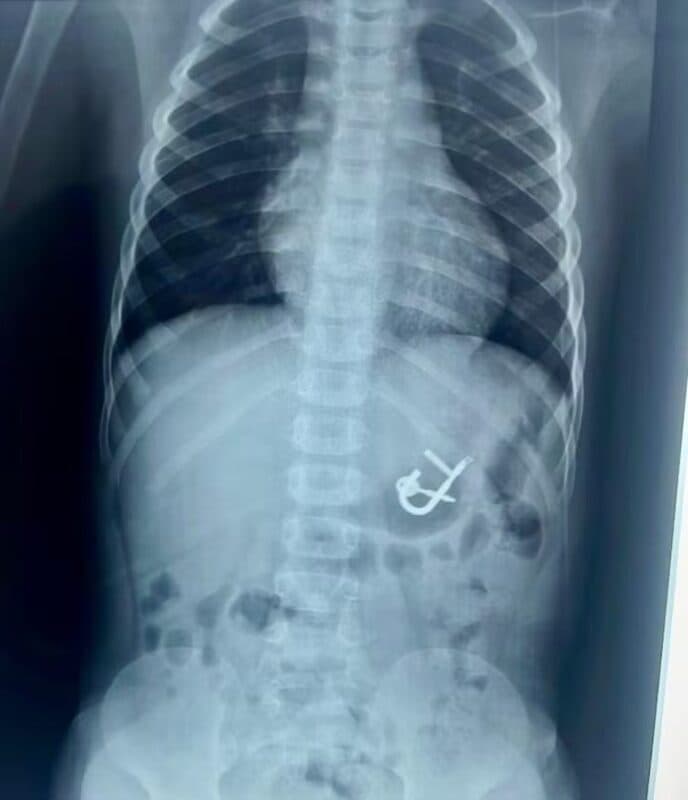

Cadeado estava alojado no estômago do menino de quatro anos em Cedro, Sertão de Pernambuco - Foto: Divulgação/Hospital Regional Inácio de Sá